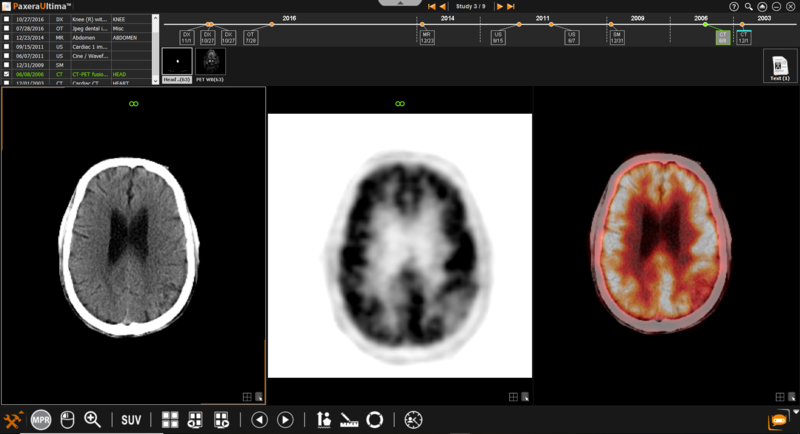

9.3.2. Manual Fusion

To conduct the fusion manually, follow the instructions below:

1.      Hold in the ‘Ctrl’ button on the keyboard and select the CT and PET image of interest.

2.      Right click on one of the selected images, a dropdown list will appear, click on ‘2D fusion’

3.      The layout will adjust automatically to accommodate for the rendered fusion image: